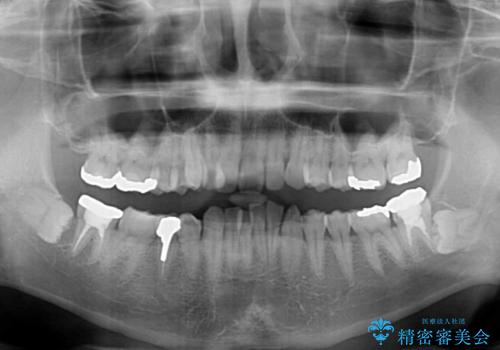

【モニター】八重歯と正中のずれた歯列 片顎抜歯のワイヤー矯正

- 上顎の八重歯と正中のズレを気にして来院された患者様です。

八重歯による叢生は著しく、それにより上顎の正中が大きく右にずれている状態でした。

口元の突出感は感じていなかったことと、奥歯の咬み合わせを考慮し、上顎のみ左右の第一小臼歯を抜歯してワイヤー装置にて矯正治療を行うこととしました。